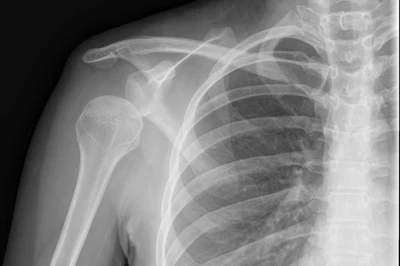

هشتگ دررفتگی شانه